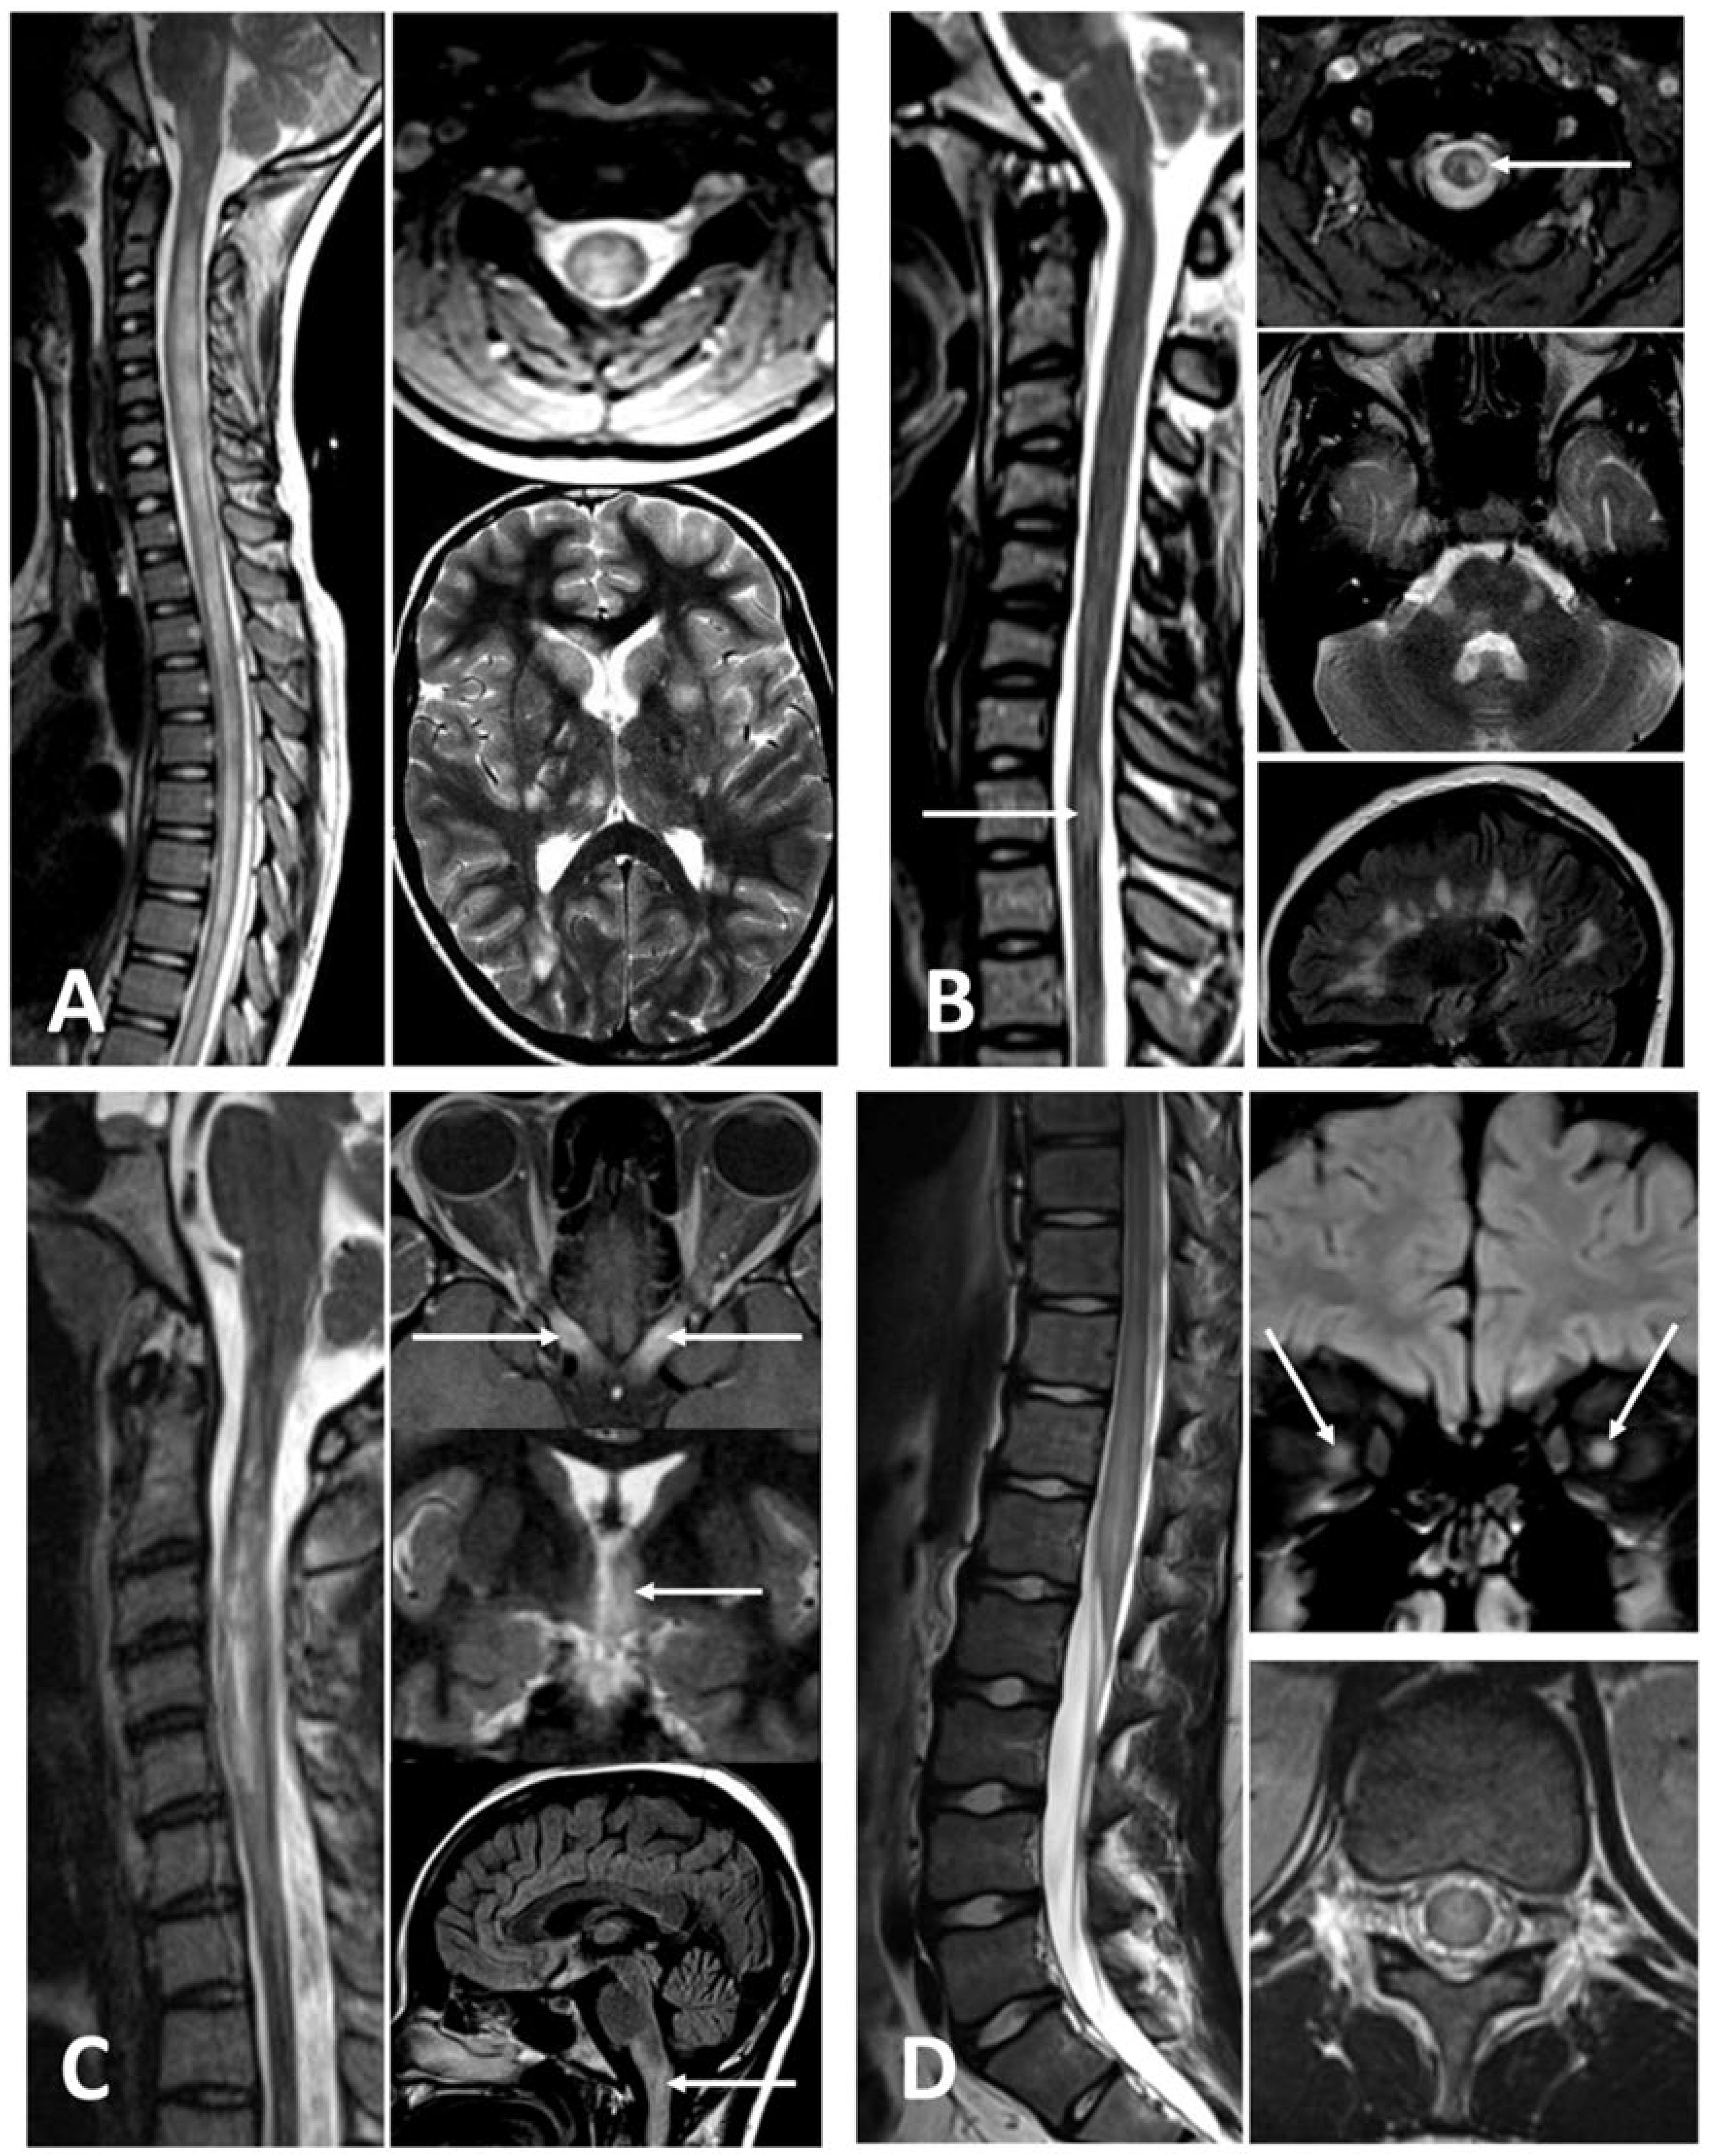

3.3. Inflammatory

3.4. Infectious

3.5. Neurodegenerative, Metabolic, and Nutritional